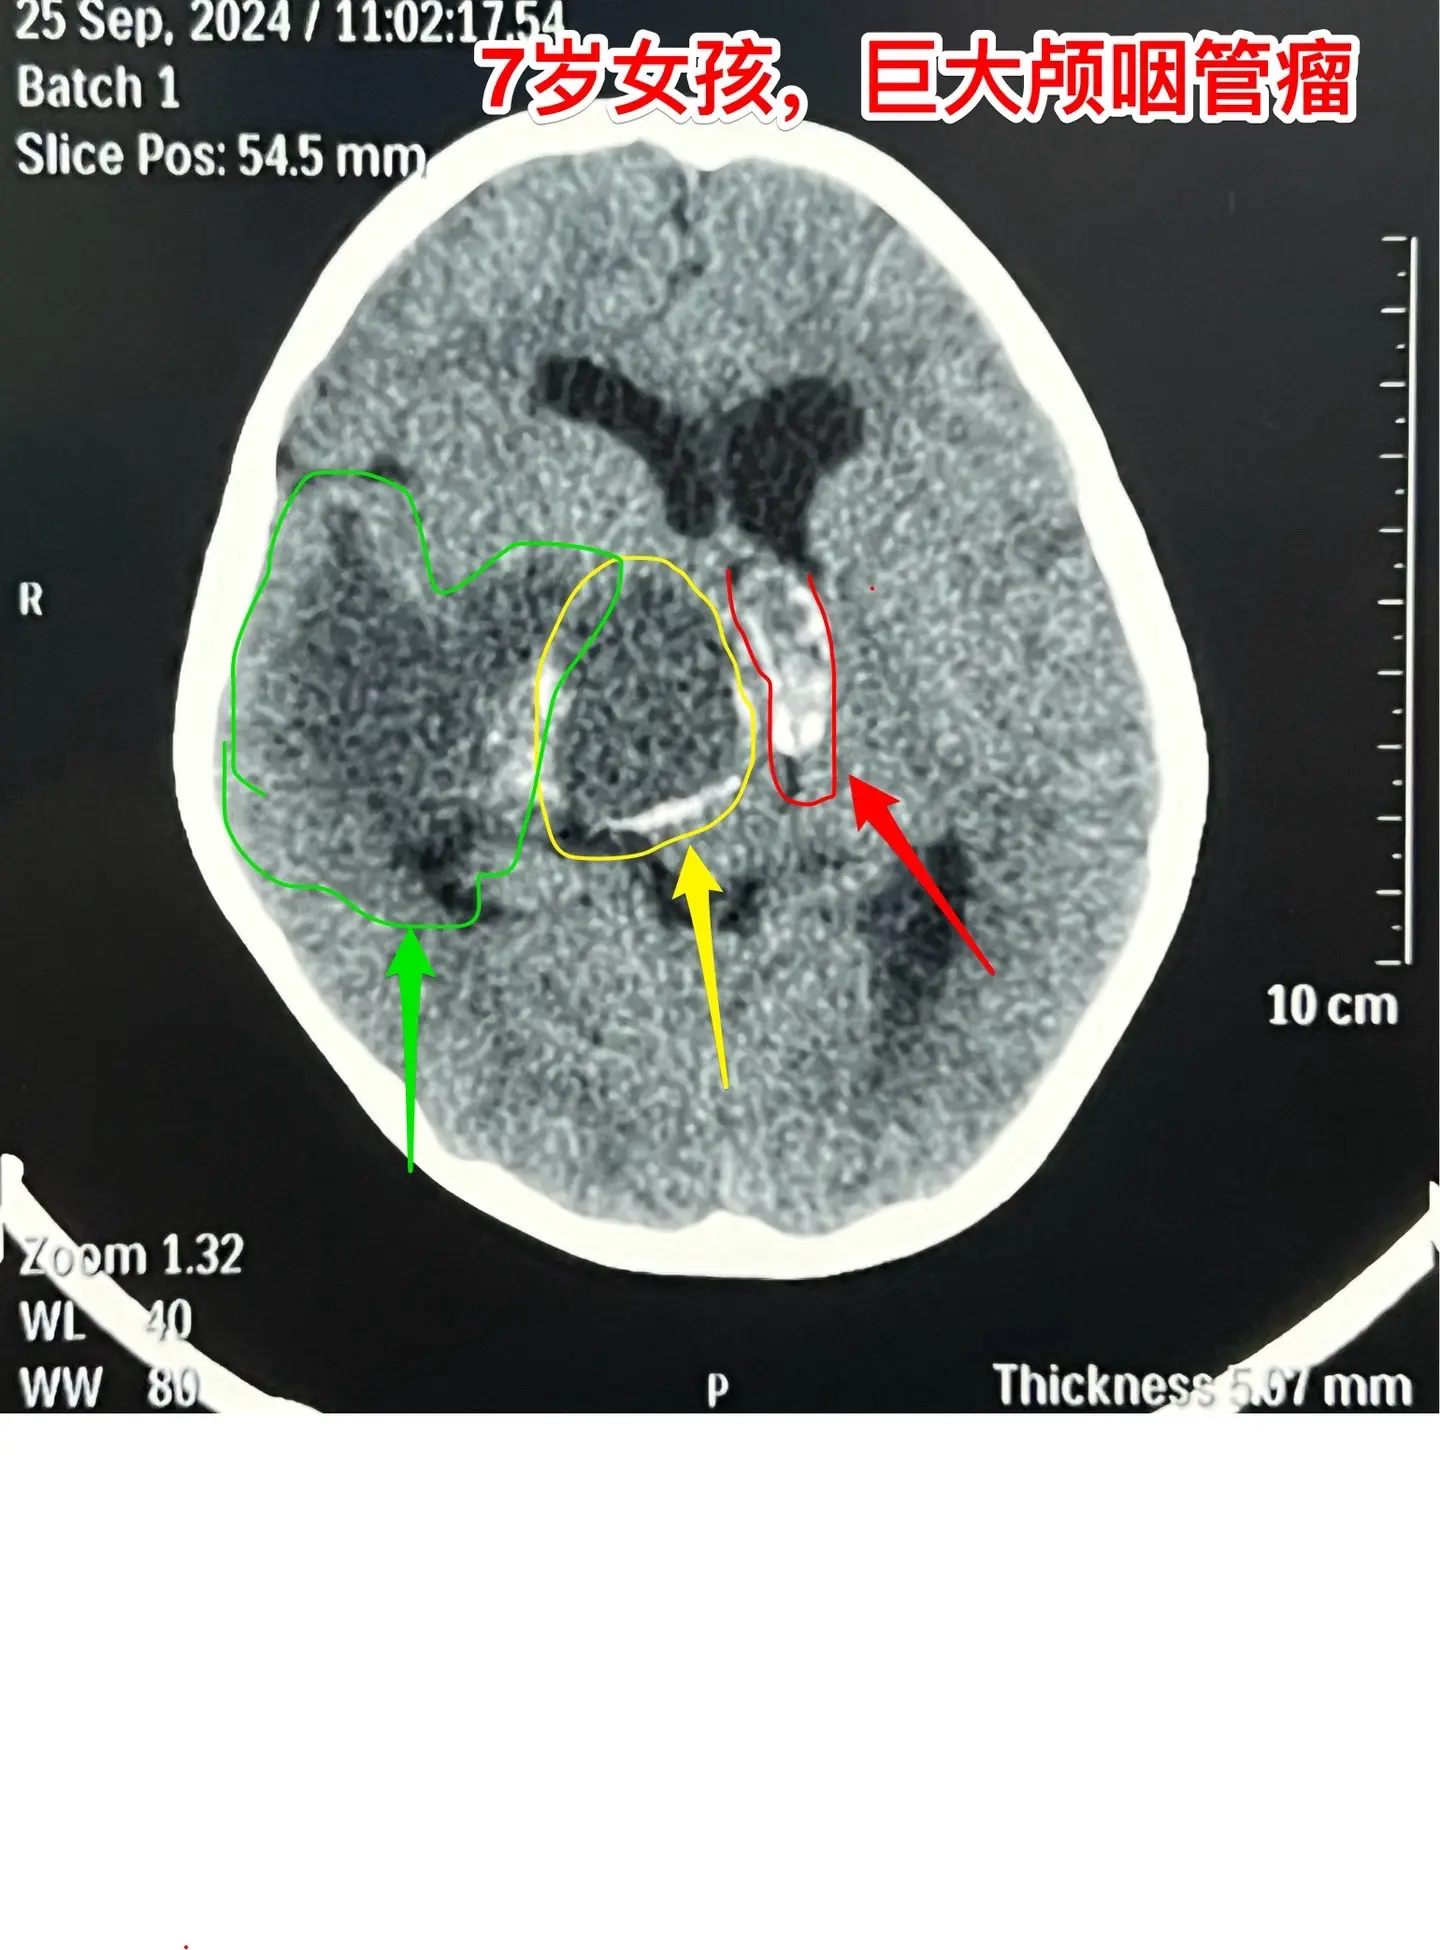

漳州市女孩子脑部长了巨大的颅咽管瘤。7岁漳州市女孩子,入院前两个月经常出现呕吐,按胃肠疾病治疗无效。入院前20天出现左侧上下肢活动力弱,伴有左上肢抖动。在厦门某医院经CT检查发现是脑部肿瘤。 从头CT可以看出这是典型的颅咽管瘤,鞍区有很大的钙化团块,小块肿瘤侵入第三脑室,肿瘤囊向右侧颞部及基底节区生长并有推挤压迫效应。手术有难度啊! 我们的手术入路设计思路:肿瘤起源点在中线,有大块钙化,是手术的难点,故以中线方向为主攻方向,争取将肿瘤的起源点及钙化完全切除!而向右侧颞部生长的肿瘤囊虽然体积大,只是肿瘤的扩张产物,切除的难度并不大,故右侧裂方向只需迂回攻击即可搞定。按这个思路设计手术方案后,手术中也有出乎意料的环节。鞍上的肿瘤钙化块又大又硬,花费很大精力才能将其体积减小,从视交叉前间隙取出。肿瘤囊从颈内动脉下方侵入颞叶,一部分囊自颞部向中线方向返折嵌入到基底节区。如术前所料,这部分囊性肿瘤切除难度不是太大。肿瘤最终得到完全切除,手术后患儿精神好,四肢活动自如。